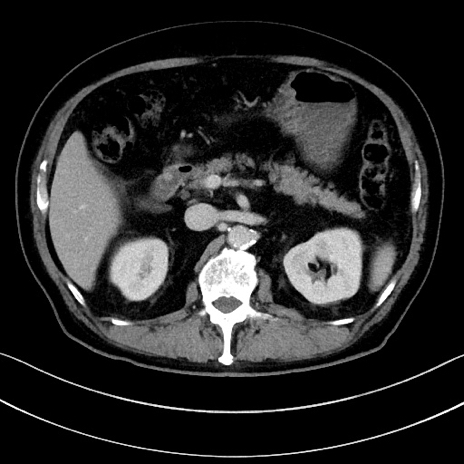

症例15(横断像)

【症例】70歳代男性

【主訴】腹痛

【現病歴】今朝から腹痛あり。全体的に痛い。特に左上の方。排ガスが今日はない。冷や汗が出る。

【既往歴】直腸癌術後

【身体所見】左側腹部〜上腹部に圧痛あり。腹膜刺激症状明らかなではない。軽度反跳痛。左下腹部に術後瘢痕あり。

【データ】WBC 7700、CRP 0.02